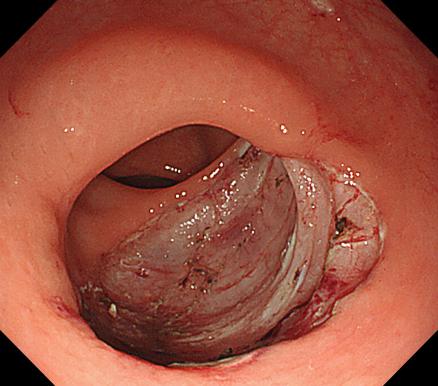

食管靜脈曲張 內鏡下套扎術

食管靜脈曲張套扎術(EVL):治療食管靜脈曲張、胃底靜脈曲張破裂出血、藥物止血無效者;既往有食管靜脈曲張破裂出血史者預防再出血。